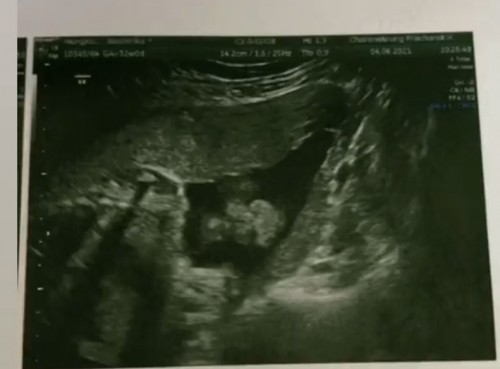

อันนี้ใช่หน้าน้องไหมคะ เหมือนได้ยินคุณหมอบอกว่าอันนี้หน้าน้อง แต่เราไม่รู้ว่าปากหรือจมูกอะไรอยู่ส่วนไหน ฝากรพ.รัฐค่ะแล้วหมอที่ซาวด์เป็นนศ.แพทย์มีอาจารย์หมอคอยอธิบายข้างหลังแต่อธิบายเป็นศัพท์แพทย์ให้นศ.ฟังนะคะ เราเลยไม่แน่ใจ

จมูก และริมฝีปากค่ะ ริมฝีปากน้องปิดสนิทดีค่ะ บน-ล่าง คุณแม่ตะแคงภาพมองดีๆค่ะ 🥰🥰

ตอนไปซาวด์32wพอดีค่ะ